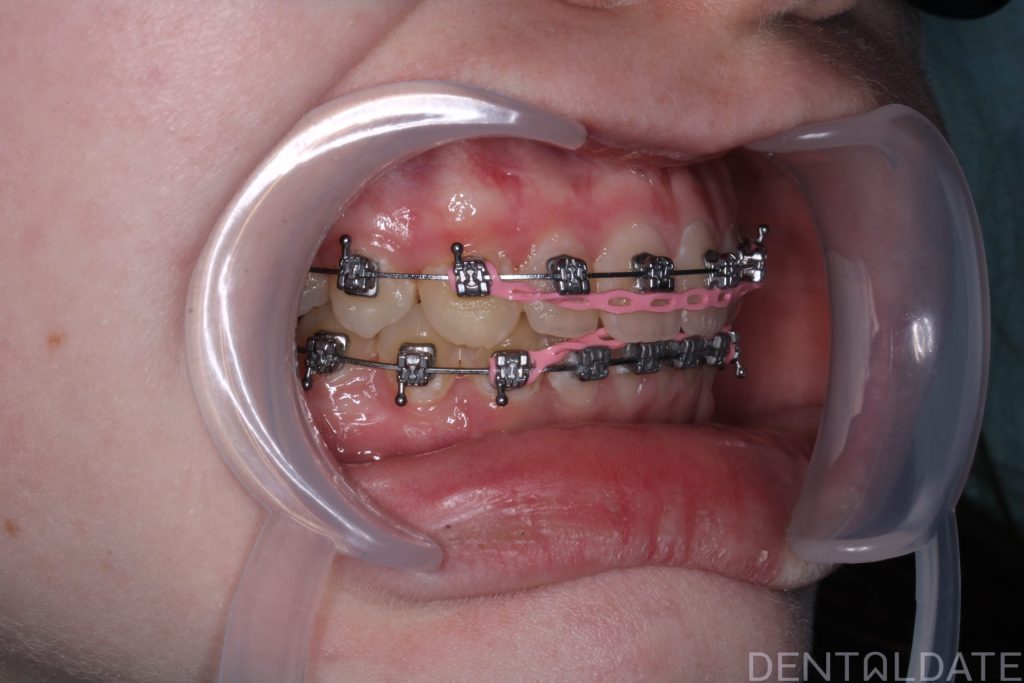

Orthodontic treatment lasted 10 months; currently, the patient is preparing for braces removal.